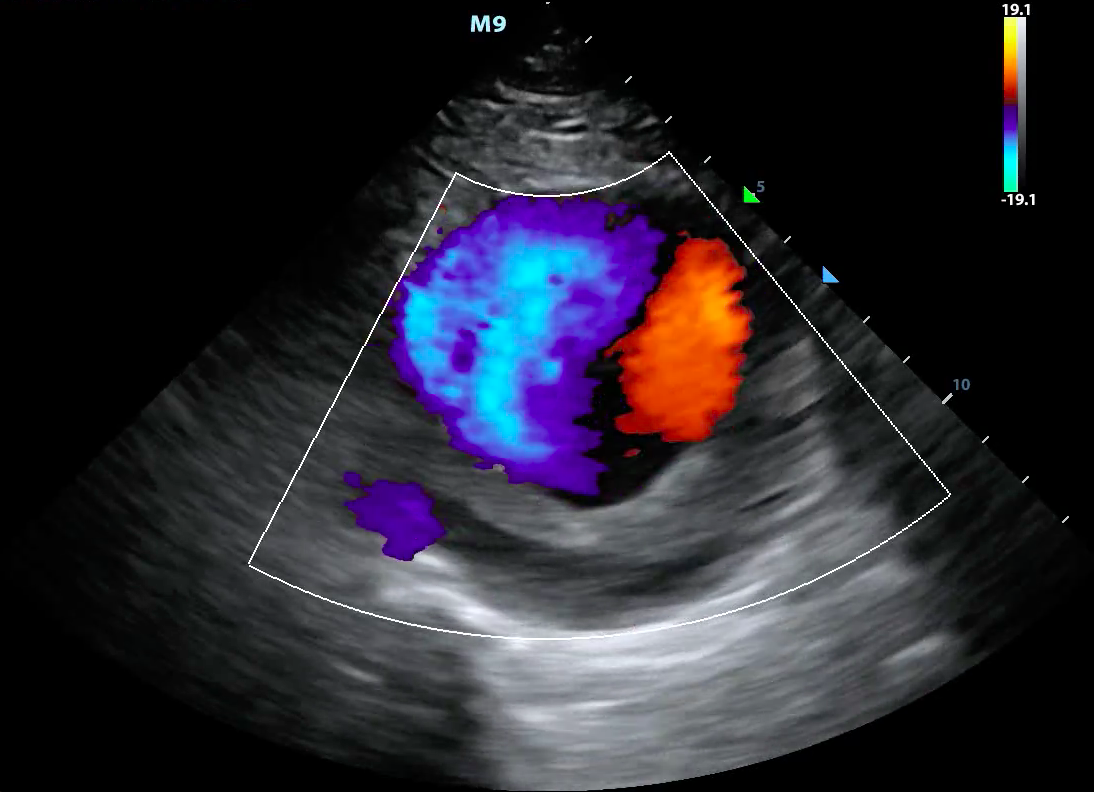

- Doppler modes examine the characteristics of direction and speed of tissue motion and blood flow and present it in audible, color or spectral displays

- Utilizes a phenomenon called ‘Doppler shift,’ which is a change in frequency from the sent to the returning sound wave

- These changes or ‘shifts’ are generated by sound waves reaching moving particles.

- The change of frequency/amount of shift correlates with the velocity and direction of particle motion

- Color Doppler ultrasound is also called color-flow ultrasound.

- It is used to show blood flow or tissue motion in a selected two-dimensional area

- Direction and velocity of tissue motion and blood flow are color coded and superimposed on the corresponding B-mode image (Figure 3, Video 2)

- Typically, red depicts movement towards the transducer, while blue depicts movement away from the transducer

- Figure 3. Color doppler showing turbulent blood flow in a large abdominal aortic aneurysm

Video 2. Color doppler showing turbulent blood flow in a large abdominal aortic aneurysm